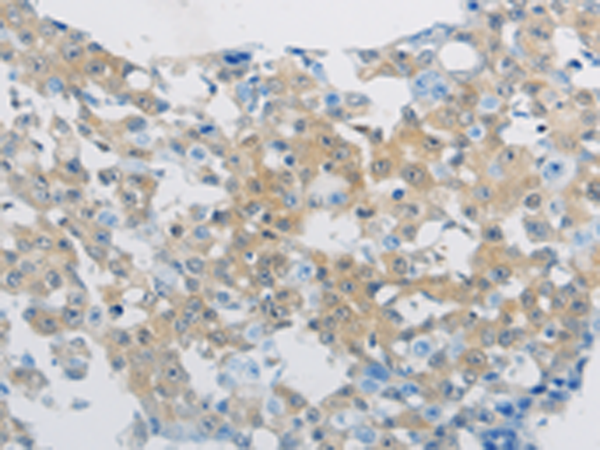

分类: 科研抗体货号: P11280别名: 24p3, MSFI, NGAL应用: WB,IHC反应种属: Human